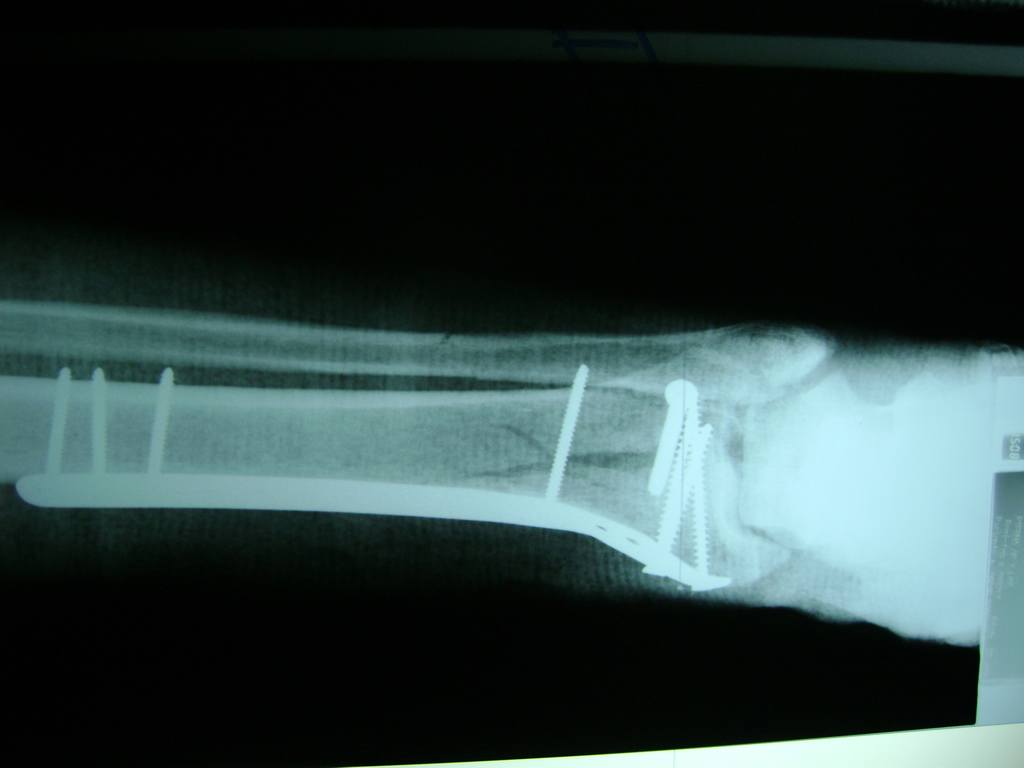

Cirugías de Codo - Perone y Tibia

Aunque cada uno de estos huesos puede fracturarse por separado, normalmente la rotura es una lesión que se produce de forma conjunta

La mayor parte de las roturas implican a la parte proximal del hueso (parte del hueso próximo a la rodilla) o a la parte distal (parte del hueso cerca del tobillo).

Debido a la fina cobertura de piel que recubre la tibia y el peroné, las fracturas generalmente son abiertas, es decir, el hueso roto rasga la piel, atravesándola. Las fracturas de tibia y peroné generalmente se producen por un fuerte impacto o torsión.